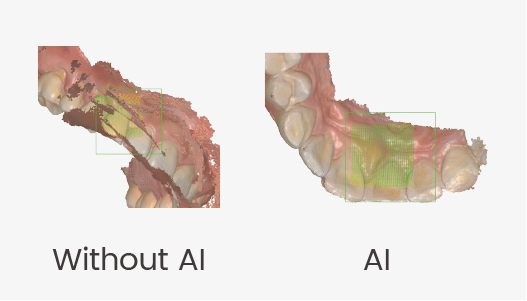

| Ai scan

Automatically identifies and fillters out unnecessary soft tissue dataduring scanning resulting in a quicker and cleaner scan process. |